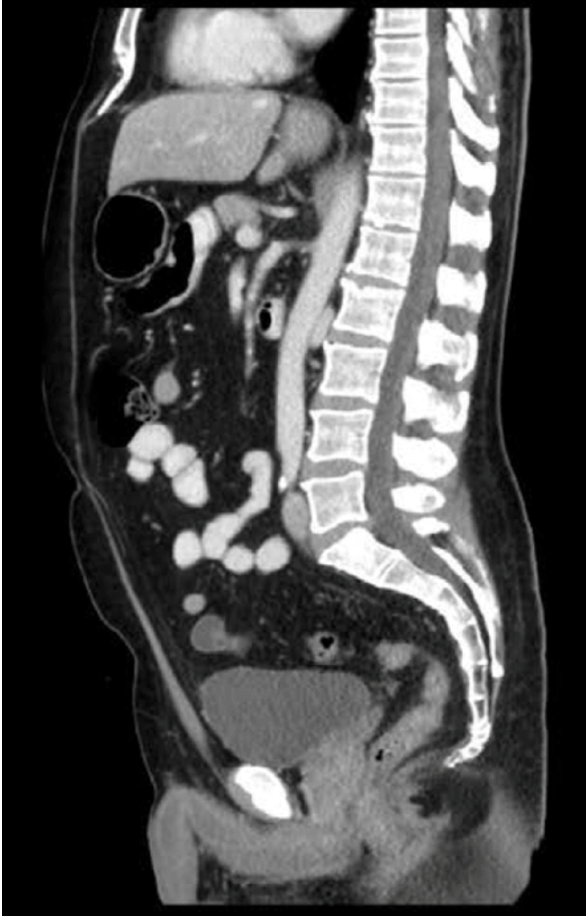

Q

Hvilken CT-projektion er vist?

A

• Sagital